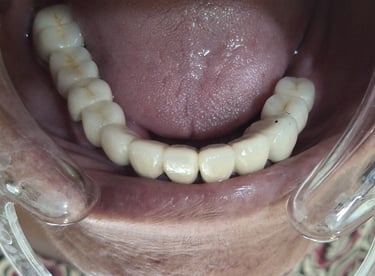

Professional Teeth Cleaning in Shyamal, Ahmedabad

Gentle, properly performed and tailored teeth cleaning for each person giving you comfort, safety and visible results. People from Shyamal and nearby areas of Ahmedabad visit our clinic for comfortable and very effective teeth cleaning.

All images shown here are real teeth cleaning cases treated at our clinic with patient consent.

Professional teeth cleaning helps remove plaque, tarter, and surface stains that regular at home brushing can not.

At Shree Dental Care, teeth cleaning is performed gently with focus on patient experience, comfort and long term oral health.

If you are looking for gentle teeth cleaning in Shyamal, Ahmedabad, you can book an appointment with our clinic.